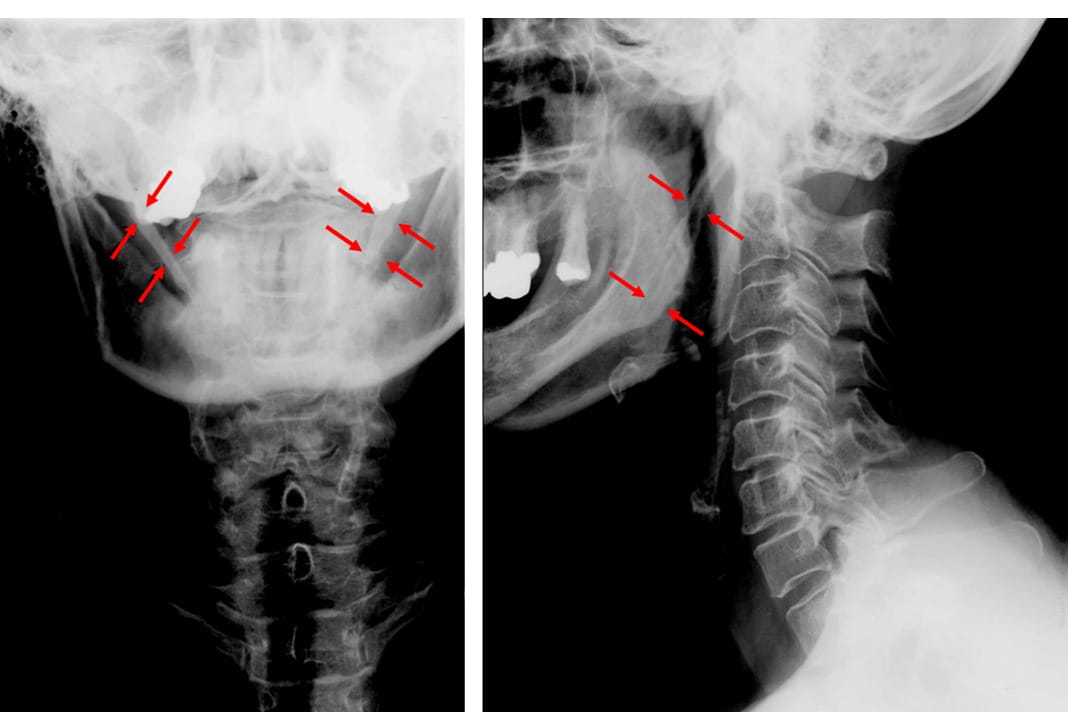

The styloid process is the small pointy bone located right below the ear. A normal styloid process is 2.5 to 3 cm in length. Any longer than 3 cm is considered elongated, which can spontaneously arise over time. The result of the elongation often causes pain in the ear, neck, head, mouth, throat, and face.

A thorough examination through physical evaluation and imaging is needed to eliminate other conditions and confirm eagle syndrome. To firmly confirm eagle syndrome is through imaging within the standard protocol through radiographs or CT. In dentistry, it can be seen on a panoramic radiograph (see Figure 1) and then referred to their physician for further evaluation.